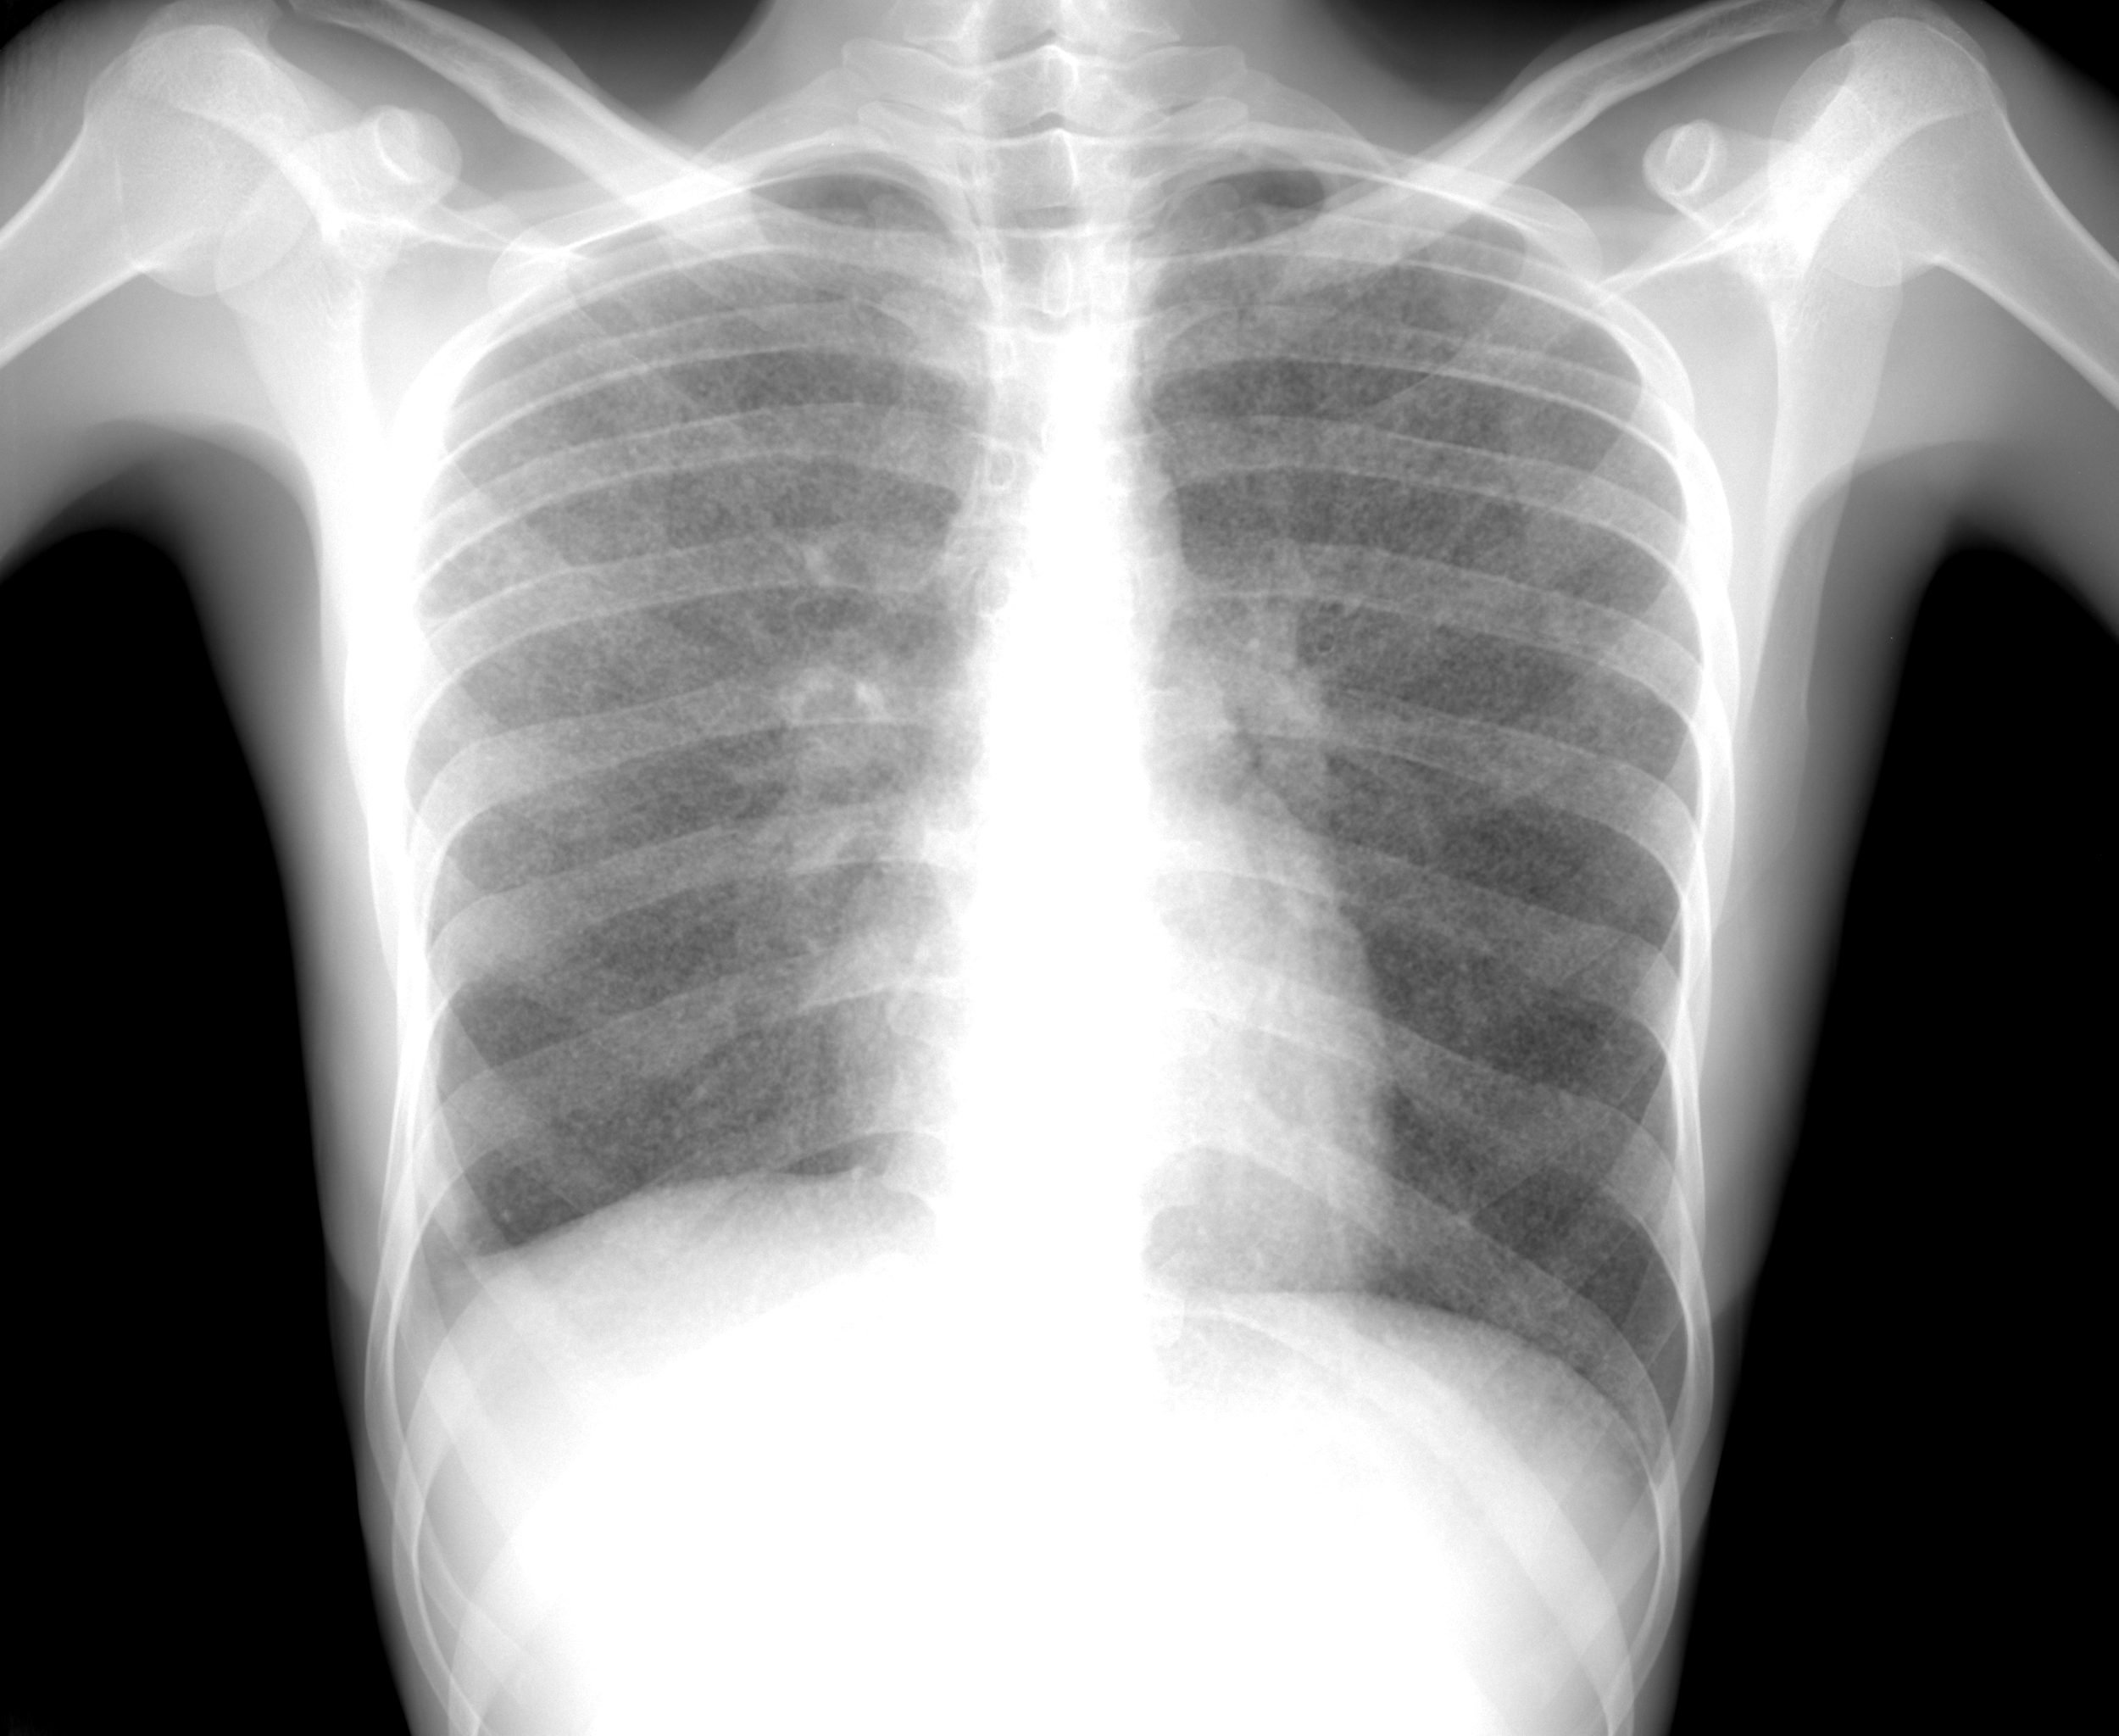

Снимок легких при туберкулезе является важным методом диагностики этого заболевания. На рентгеновских снимках можно увидеть изменения в легких, которые свойственны туберкулезу.

Фотографии снимков легких при туберкулезе

В данной статье представлены многочисленные фотографии снимков легких при туберкулезе, чтобы помочь вам понять, как выглядят изменения легких на рентгеновских снимках при этом заболевании.